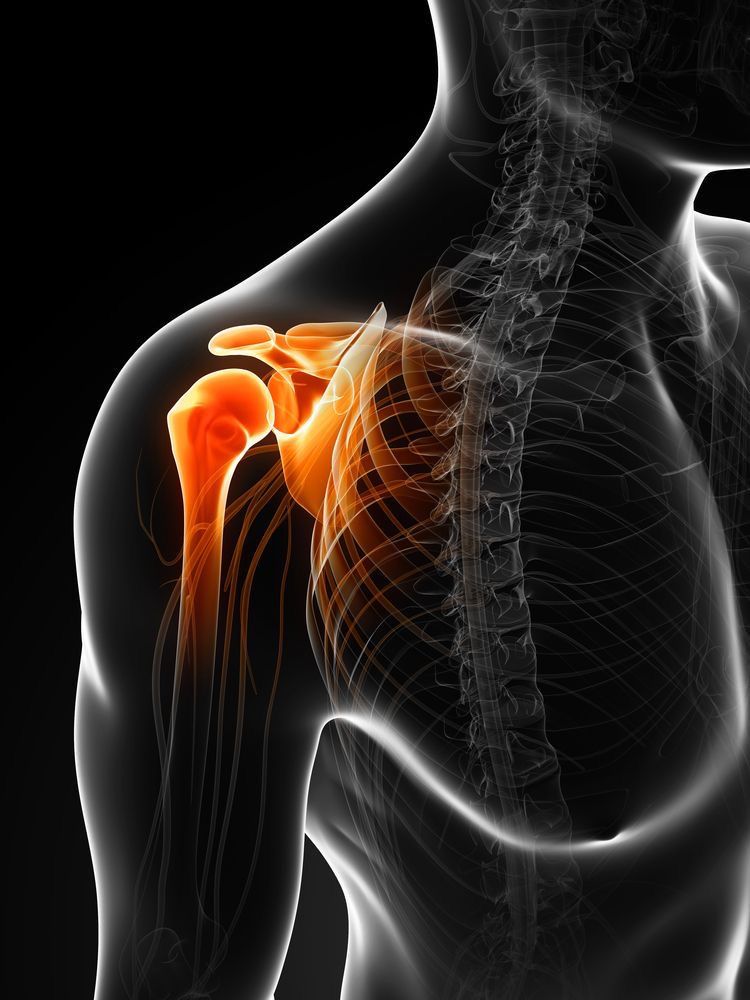

La actividad física es esencial para la salud, pero también puede generar lesiones si no se realiza correctamente:

- Rodillas y tobillos: esguinces y tendinitis por correr o hacer ciclismo en terreno irregular.

- Hombros y codos: sobrecarga en deportes como natación o tenis.